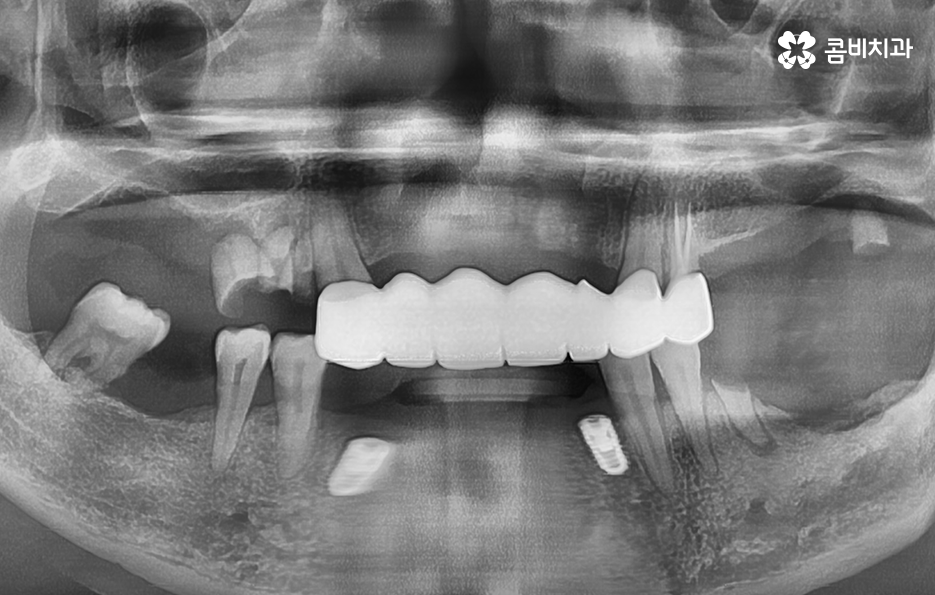

고령의 환자분들의 경우에는 잇몸 뼈의 상태 뿐 아니라 전신질환, 회복력을 함께 고려해야 하기 때문에 치료 계획에 있어서 보다 섬세하게 체크해야 하며 환자분의 잇몸 뼈 상태와 전신건강 그리고 경제적인 상황 등을 고려할 때 전체임플란트를 하게 되는 경우도 있지만 위 환자분의 사례처럼 임플란트를 최소한으로 식립하여 임플란트의 보철물을 연결하여 치아의 기능을 회복하는 경우도 있는데요

치주염 발치 해야 하는 상황으로 대부분의 치아를 잃게 된 경우이거나 임플란트를 여러개 식립하기에는 경제적 부담이 크다면 임플란트의 식립 개수는 최소화하고 보철물을 틀니처럼 사용하시는 경우도 있는데요. 앞니의 경우 식사 시에 치아에 받는 압력이 어금니에 비해 적은 편이지만 어금니의 경우 충분한 저작력을 유지하기 위해서는 충분한 두께의 잇몸 뼈에 임플란트를 식립해야 하기 때문에 잇몸 건강의 중요성에 대해 꼭 늦지 않게 신경써주시길 바라고 있어요